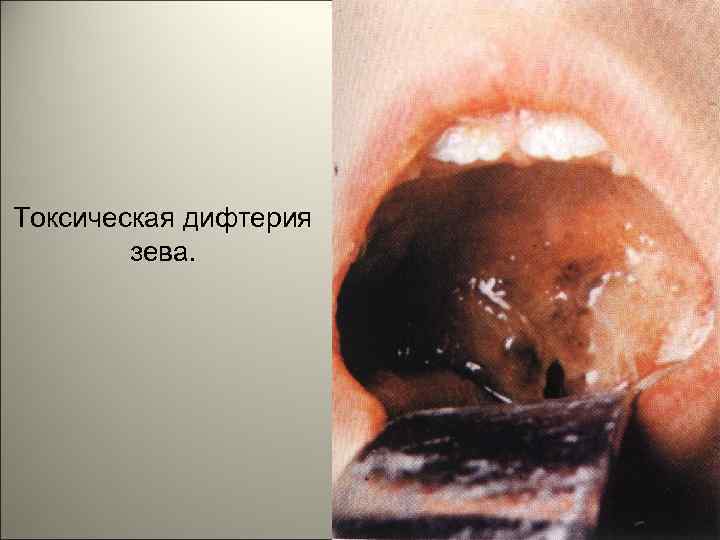

• В результате из сосудов выходит жидкая часть крови, богатая белком. Содержащийся в ней фибриноген при контакте с некротизированной тканью превращается в фибрин, образуя фибринозную пленку. На участках, покрытых многослойным эпителием (зев, глотка), возникает дифтеритическое воспаление, на слизистых оболочках, покрытых однослойным цилиндpичecким эпителием (гортань, трахея, бронхи), развивается крупозное воспаление. 114

• Клинически выделяют две основные формы — дифтерию зева и дифтерию гортани. При дифтерии зева местные изменения наблюдаются в миндалинах — ангина. Типично фибринозное воспаление миндалин с переходом фибринозных плёнок на дужки и мягкое нёбо. Плёнки плотно связаны со слизистой оболочкой, долго не отторгаются, что способствует интоксикации. Лимфатические узлы шеи увеличены за счёт некрозов и отёка, который может распространяться на всю шею и грудь. 115

Токсическая дифтерия зева. 118